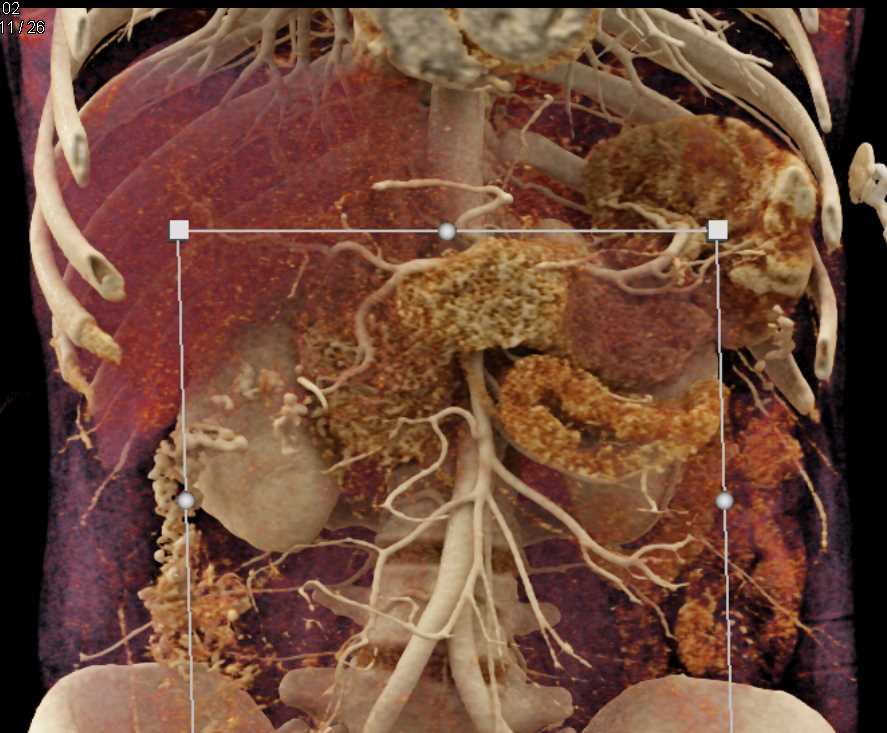

Neuroendocrine Tumor Pancreas